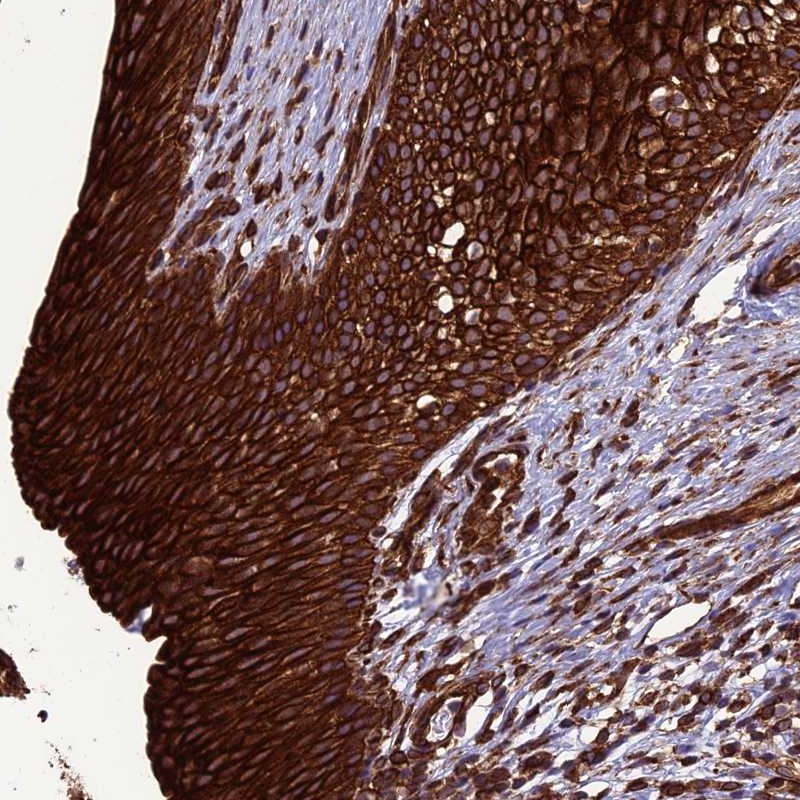

Immunohistochemical staining of human urinary bladder shows strong cytoplasmic and membranous positivity in urothelial cells.